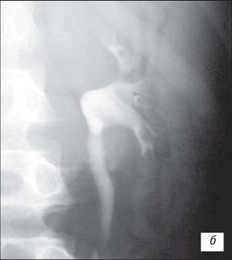

Висхідна цистографія

На даній рентгенограмі спостерігаємо активно-пасивний міхурово-сечовий рефлюкс зліва 4 ступені. Виражена дилатація чашечко-мисочкової системи, деформація чашок.

а – у фазі максимального наповнення сечового міхура, пасивний рефлекс; б – у фазі сечовипускання, активний рефлекс.